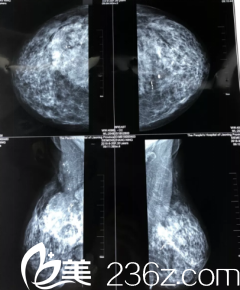

那時候剛興起注射隆胸,露西就拉著好朋友一起直接跑去美容診所,注射了奧美定。但是那時候她并不知道注射到自己的胸部是什么的東西,年輕的她并沒有考慮那么多。注射隆胸后的幾年間她一直沉浸在自己重新?lián)碛辛孙枬M的胸部的滿足感之中。

在加拿大偶然的一次日常體檢中,醫(yī)生發(fā)現(xiàn)露西的胸部有一個硬塊,但是由于國外沒有奧美定這種東西,他們不能分辨硬包快到底是什么。

這一次,醫(yī)生很明確的告訴她,她胸部的奧美定注射物發(fā)生感染了,建議她馬上就安排手術(shù)吸出注射物。聽到這話露西馬上給當年一起進行注射隆胸的好朋友打電話。

兩天后,露西便從加拿大回到了西安,第二天一早便來到醫(yī)院,進行胸部奧美定注射物取出手術(shù),醫(yī)生告訴露西,取出的難度比較大,但是會盡他所能的清理干凈。